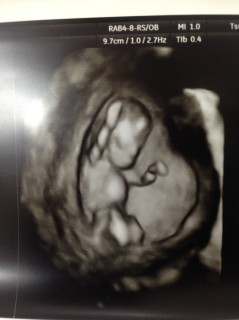

割と鮮明な4Dで撮ってもらいました。5.9ミリだそう。 全く実感がなかったのに、こんな小さいのに一人前に人間で感動しました! 指しゃぶりをしたり途中から寝たりしてました。笑

エコー中赤ちゃんは寝ていたようで、動くところは見れませんでしたが、のびのびと育っていました(*´ω`*)頭の大きさは23mm